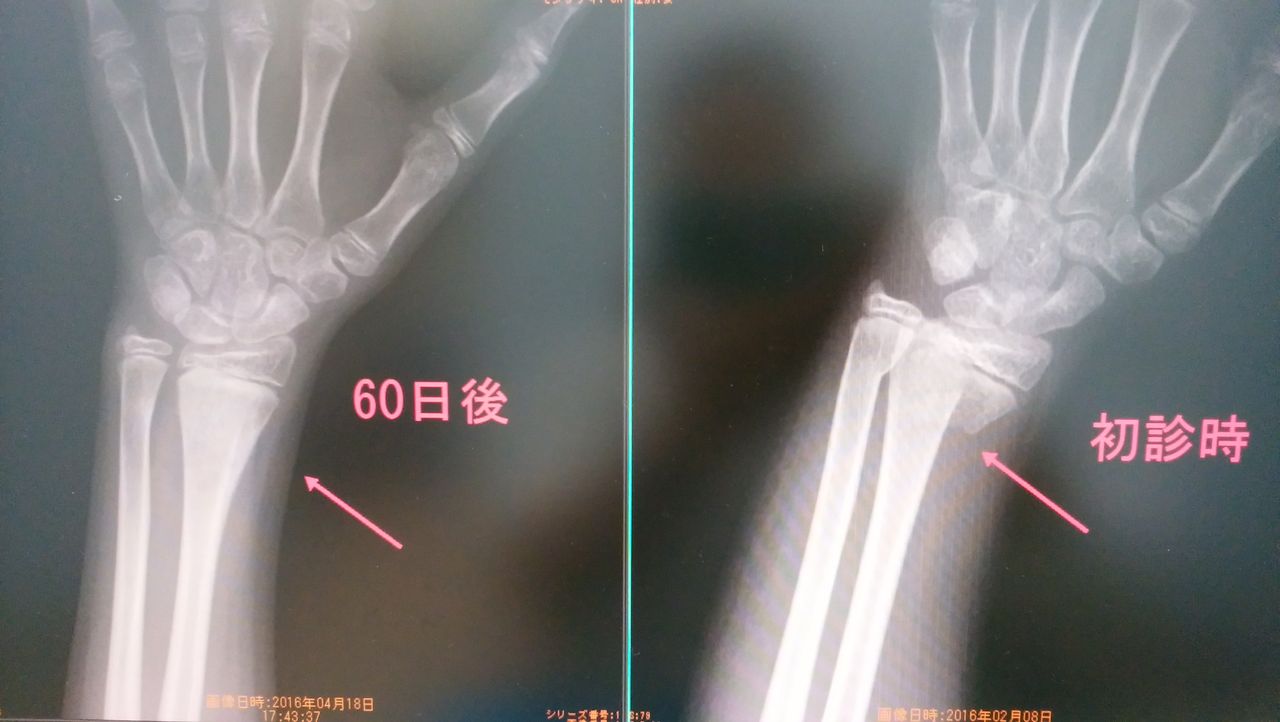

かなりずれているスミス骨折です、

手の形がなかったぐらいですが、手術せずに、

きれいになおりました